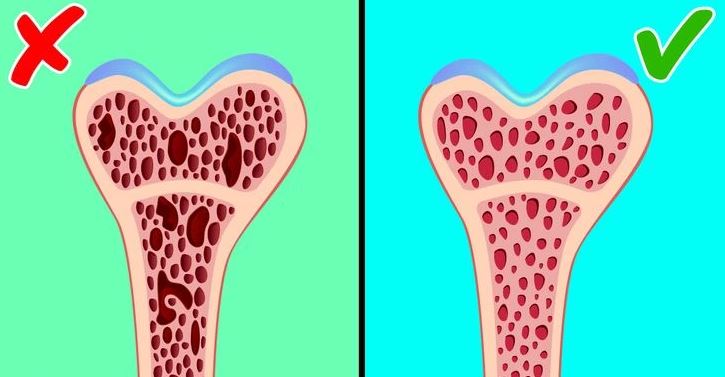

#2 Pokles hustoty kostí

Kosti si vyžadujú mechanické namáhanie, aby si zachovali svoju hustotu. Vo vesmíre má nedostatok gravitačného zaťaženia za následok stratu hustoty kostí, najmä v kostiach, ktoré nesú váhu, ako sú bedrá a nohy. Astronauti môžu stratiť približne 1 % kostnej hmoty za mesiac, čo je výrazne vyššia miera ako strata pozorovaná u starších ľudí na Zemi. Tento úbytok zvyšuje riziko zlomenín a predstavuje výzvu pri dlhodobých misiách.